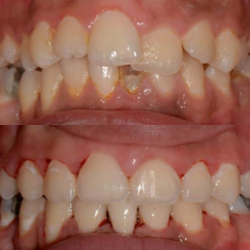

Full Mouth Reconstruction